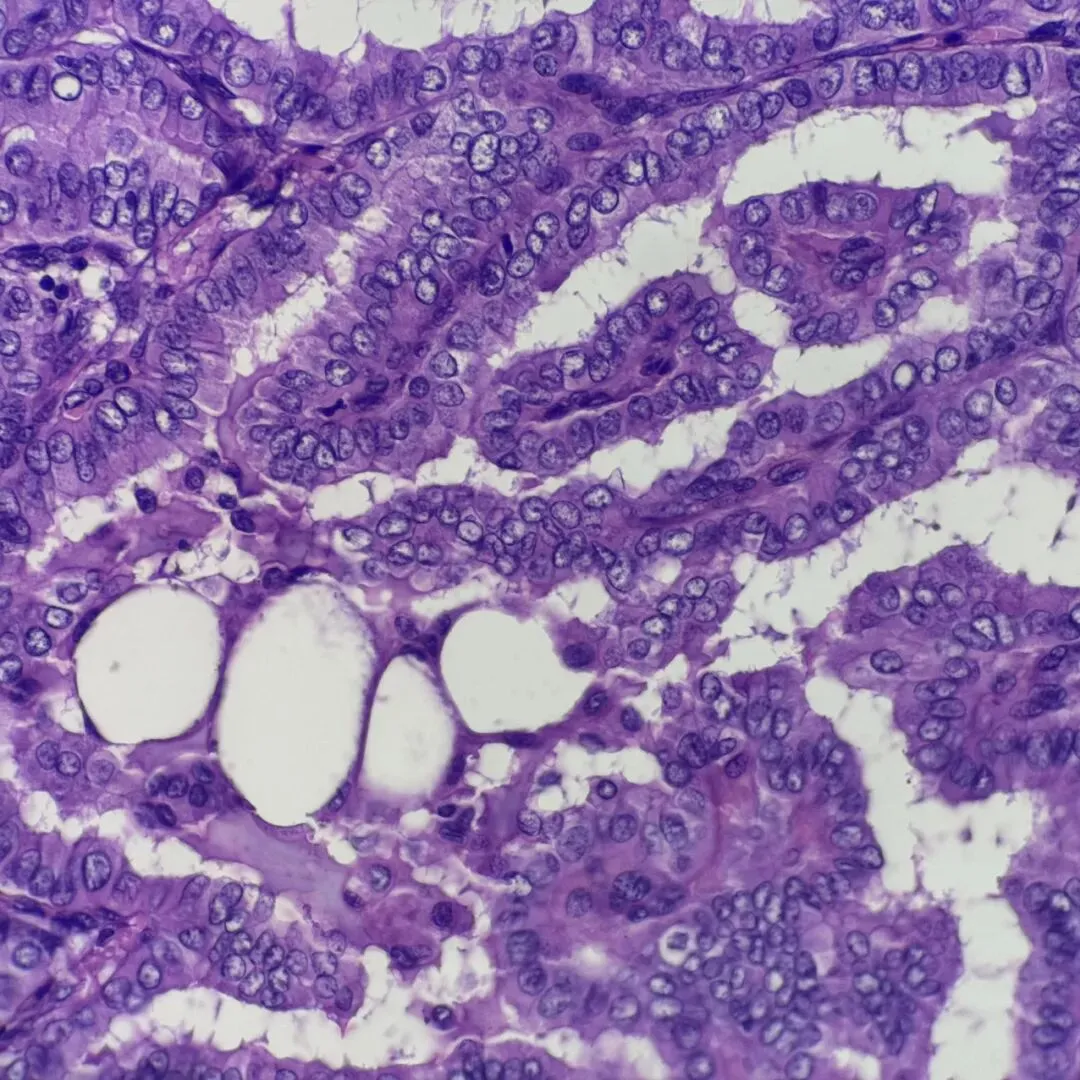

图3

图3-4 组织学:可见含纤维血管轴心的乳头,毛玻璃样核,核拥挤重叠,核沟易见。